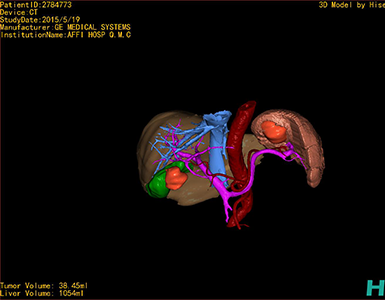

将0.625mm双源薄层CT资料的静脉期和动脉期Dicom格式文件导入海信CAS系统。

通过调节窗宽窗位调整CT序号,对肿瘤,肝实质,胆囊,下腔静脉,肿瘤,肝动脉、门静脉及肝静脉等进行三维重建;系统自动计算肿瘤体积和肝脏体积。

模拟手术操作,自动计算切除肿瘤体积。肝脏体积为1054ml,肿瘤体积为38.45ml,肿瘤体积为肝脏体积的3.6%,通过比对50-60岁正常肝脏体积为1330.41±329.13 ml,通过术前模拟手术,精准判断切除后剩余肝脏体积能耐受,避免肝衰竭发生。

术前三维重建:

重建图片